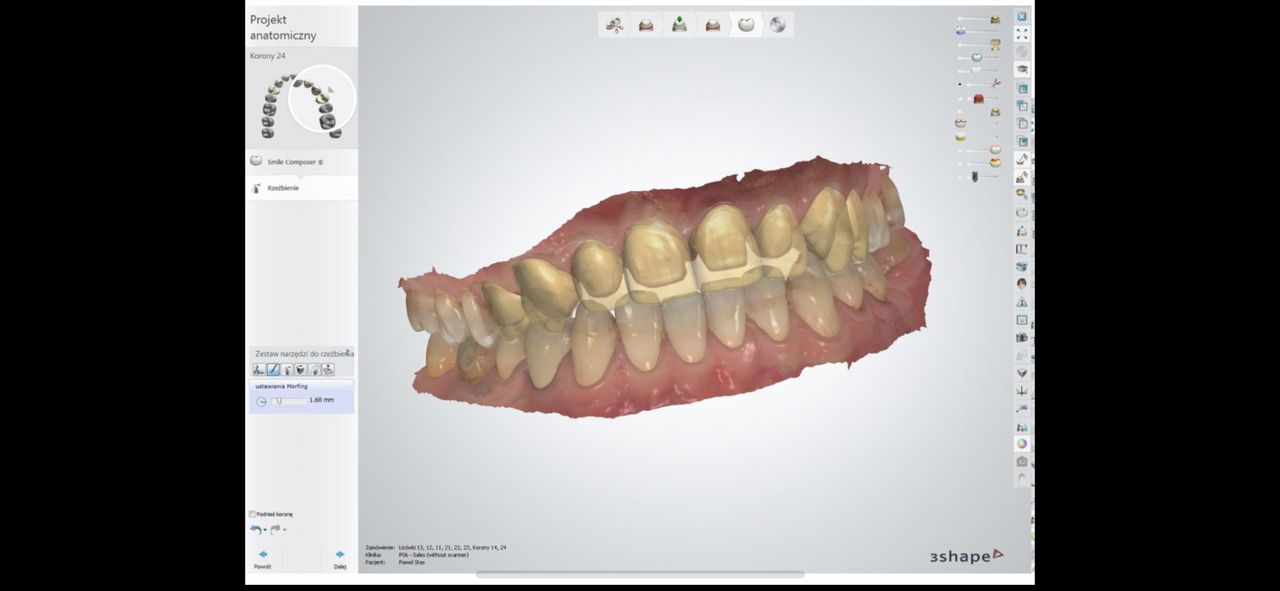

Ukończyłem Łódzką Akademie Medyczna, na wydziale stomatologicznym . W 2007 roku uzyskałem tytuł specjalisty w dziedzinie protetyki stomatologicznej. Regularnie pogłębiam wiedze z zakresu stomatologii o czym świadczą zdobyte przeze mnie certyfikaty . W chwili obecnej prowadzę NZOZ Duodent , specjalistyczny gabinet protetyczny na Widzewie - wschodzie , przy ul. Gogola 12 . Znajdują sie tu trzy nowocześnie urządzone i wyposażone gabinety stomatologiczne. Pracujemy na sprzęcie Sterna Webera, prestiżowej szwajcarskiej firmy produkującej unity stomatologiczne...W gabinecie znajduje sie skaner wewnątrzustny MEDIR i 500 R , gdyz obecnie gabinet nasz wyspecjalizował sie w PROTETYCE CYFROWEJ

Współpracujemy z cyfrowa pracownia techniczna z Warszawy - SCAN LAB.

. W tym wypadku odległość nie ma znaczenia , gdyż wyciski w formie cyfrowej trafiają internetem do pracowni w ciągu paru sekund po ich uzyskaniu drogą skanowania w ustach pacjenta, bez zniekształceń i deformacji. CAD/CAM to supernowoczesna frezarka komputerowa, wycinająca z bloczku cyrkonu najbardziej precyzyjne elementy .